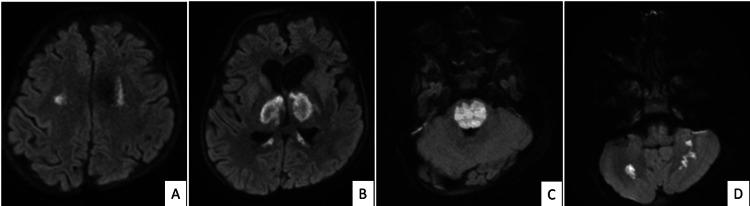

Acute necrotizing encephalopathy of childhood (ANEC) is a severe neurological disorder characterized by rapid-onset encephalopathy, often associated with viral infections. Acute necrotizing encephalopathy of childhood is associated with a very high mortality rate, and survivors may face long-term neurological sequelae. Acute necrotizing encephalopathy of childhood needs to be differentiated from its closest differential diagnosis, acute disseminated encephalomyelitis (ADEM). Most of the patients with ADEM recover, with a few of them having residual neurological deficits. We present a case of an eight-year-old boy with an acute history of fever, febrile seizures, and drowsiness. Magnetic resonance imaging revealed a symmetric tricolor appearance of bilateral thalamic lesions, characteristic of ANEC.

儿童急性坏死性脑病(ANEC)是一种严重的神经系统疾病,其特征为快速起病的脑病,常与病毒感染相关。儿童急性坏死性脑病的死亡率非常高,幸存者可能面临长期神经后遗症。儿童急性坏死性脑病需要与其最相近的鉴别诊断——急性播散性脑脊髓炎(ADEM)相区分。大多数ADEM患者可康复,少数患者有残留神经功能缺损。我们报告一例8岁男孩,有发热、热性惊厥及嗜睡的急性病史。磁共振成像显示双侧丘脑病变呈对称的三色外观,这是ANEC的特征表现。